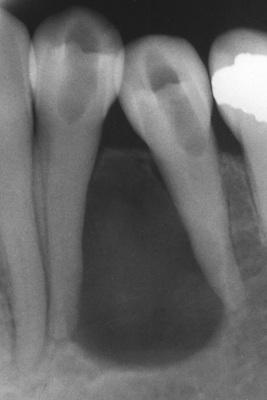

A unilocular radiolucent cyst extending along the mesial and distal roots of the unerupted tooth.

dentigerous cyst, circumferential type